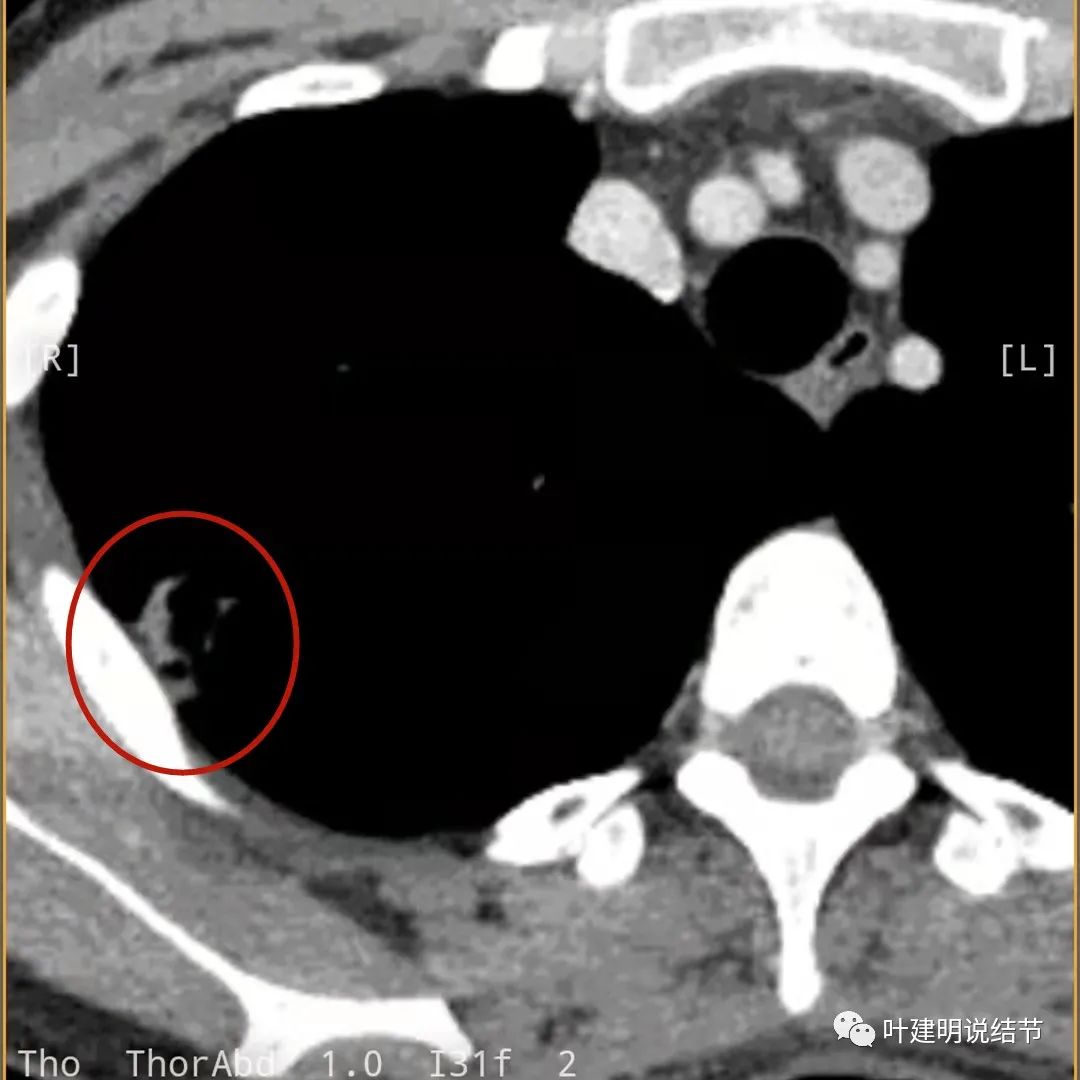

此层也见明显的低密度区域(天蓝色箭头)

胸膜处明显增厚伴低密度区域

天蓝色箭头示病灶低密度区,考虑坏死可能性大,桔色箭头示边缘凹陷无膨胀性